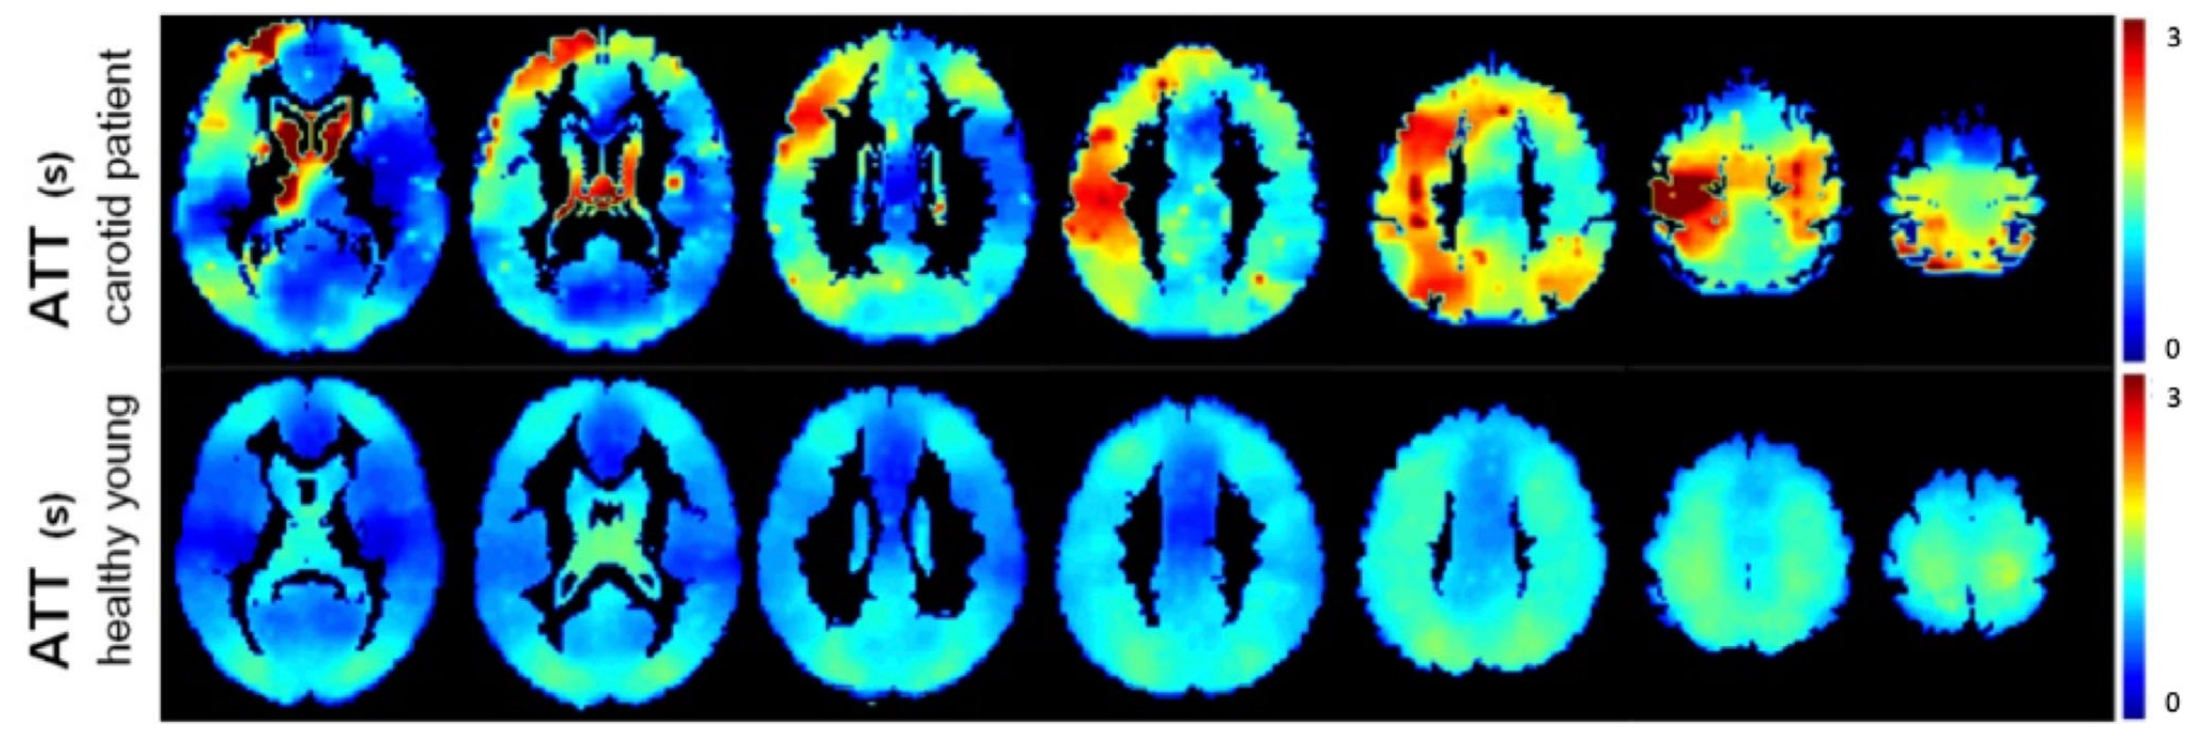

2015年共识文件中还讨论了另一种方法,即使用多PLD/多时间点ASL。在这种情况下,LD和/或PLD的时间参数在重复采集中变化。通过动力学建模组合结果数据,以产生脑血流量(CBF)和ATT的估计,估计的CBF本质上对ATT变化不敏感。(见图1)这种方法特别适用于ATT显著偏离正常的情况,例如在狭窄闭塞性疾病中(见图2),或者在个体或条件之间变化,例如在脑血管反应性研究中。ATT本身也被证明是疾病的一个重要生理标记。最后,多时间点ASL提供了提取额外血液动力学参数定量图的机会。

8f0601e8f2a2298a0bc64a270a9f1d5f.png图2:显示ATT随疾病变化的变化。最上面一行显示了颈动脉闭塞患者在不同切片上的ATT图,而最下面一行显示了9名健康年轻受试者的组平均ATT图。该数据被修正为部分体积效应,并代表了纯GM ATT的估计数。注意健康年轻受试者的左右对称性和整体ATT较低。患者同侧半球的ATT平均长于~1 s。